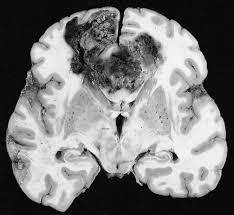

Glioblastoma: Killer cocktail combatte il cancro al cervello

Una nuova combinazione di farmaci che agiscono sul sistema immunitario, sradica una forma aggressiva di cancro al cervello, il glioblastoma,…